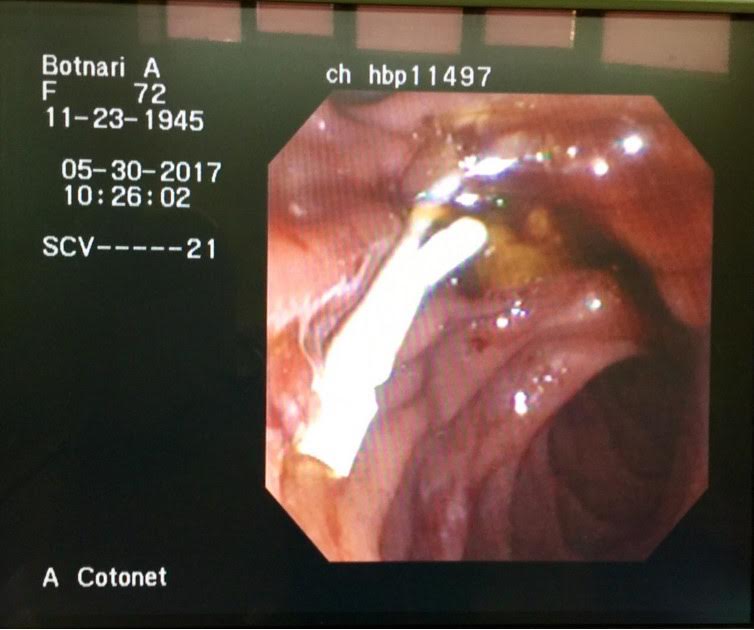

Ulterior, pe 30.05.2017 pacienta a suportat o intervenţie endoscopică miniminvazivă în cabinetul de endochirurgie a SCR. Echipa de chirurgi-endoscopiști formată din d.ș.m. Alic Cotoneţ şi Roman Bodrug, as/m Natalia Râmbu şi anesteziologică - medicul Vasile Roznovan și as/m Natalia Basnari, rezident Vadim Mârca au reuşit protezarea endoscopică a coledocului afectat neoplasic. Datorită condiţiilor moderne de lucru şi experienţei vaste pe care o posedă această echipă, aşa categorie de pacienţi primesc un răgaz confortabil pentru elaborarea conduitei tratamentului, iar gestul chirurgical tradiţional poate fi amânat pentru a fi practicat în condiții de risc minim pentru viaţa bolnavilor.